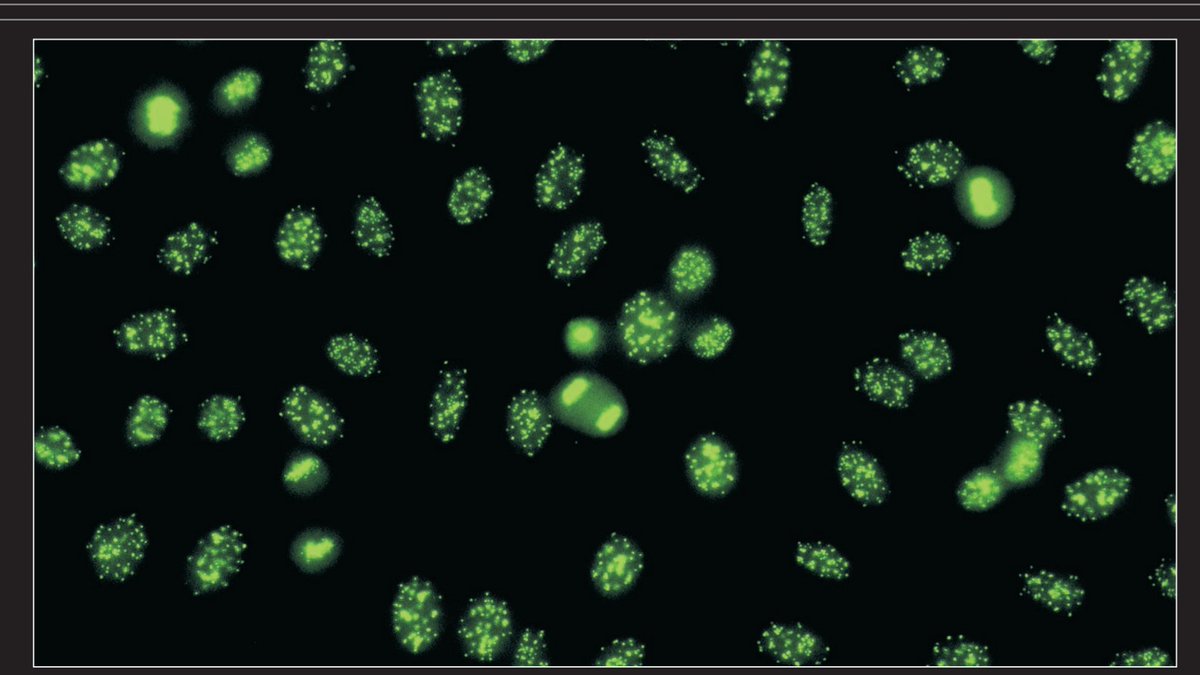

2- #Speckeld_pattern

وهو مرتبط بتشخيص Sjogren's syndrome , SLE and mixed connective tissue disorders (#MCTD)

Antibodies to Sm, RNP, SS-A/SS-B, PM-1, and PCNA antigen

نلاحظ في هذا النوع وجود ثقوب داخل النواة وقد تكون Fine or coarse

وعدم وجود Chromosome في Metaphase